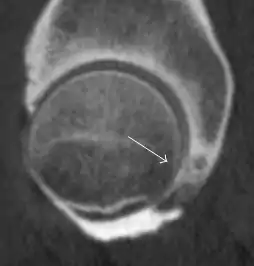

Axial CT image of pigmented villonodular synovitis eroding the posterior cortex of the femoral neck.[1]

Sagittal T2* gradient echo image showing a posterior soft tissue mass with hypointense areas secondary to hemosiderin deposition.[1]

In synovial proliferative disorders, MRI demonstrates synovial hypertrophy. In the case of PVNS, characteristic foci of low signal intensity related to hemosiderin deposition are better seen on gradient echo T2* images (Figure 7). In the case of synovial osteochondromatosis, the synovial hypertrophy is accompanied by intermediate signal cartilaginous loose bodies and/or low signal calcified loose bodies.[1]